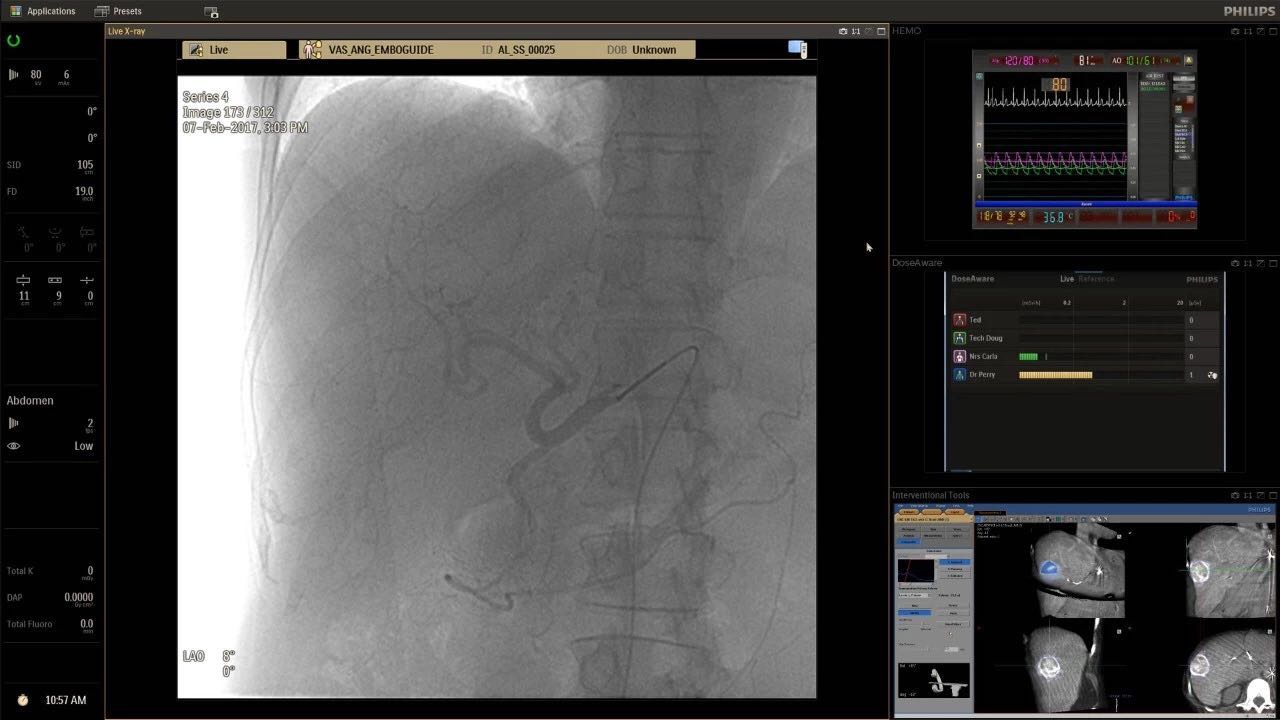

在日益復(fù)雜的干預(yù)期間,臨床醫(yī)生需要快速、輕松地可視化關(guān)鍵解剖結(jié)構(gòu)并確定手術(shù)過(guò)程中患者的變化。2019年1月17日,飛利浦宣布推出采用FlexArm的Azurion 7 C20,旨在提高圖像引導(dǎo)程序的定位靈活性。

帶有FlexArm的Azurion 7 C20 包含一系列創(chuàng)新技術(shù),使臨床醫(yī)生可以更輕松地在整個(gè)患者身上進(jìn)行二維和三維成像。當(dāng)臨床醫(yī)生移動(dòng)系統(tǒng)時(shí),圖像光束自動(dòng)保持與患者的對(duì)準(zhǔn),允許更一致的可視化并使他們能夠?qū)⒆⒁饬性谥委熒稀?/span>

可通過(guò)微創(chuàng)手術(shù)治療的疾病的范圍和復(fù)雜性繼續(xù)擴(kuò)大。相應(yīng)地,程序本身也變得更加復(fù)雜,需要來(lái)自不同學(xué)科的更多醫(yī)生在患者的桌邊,以高度協(xié)調(diào)的方式一起工作。因此,臨床團(tuán)隊(duì)需要在高度受限的環(huán)境中執(zhí)行越來(lái)越具有挑戰(zhàn)性的程序。

飛利浦表示,采用FlexArm設(shè)計(jì)的Azurion 7 C20可提供卓越的靈活性和直觀的控制。該系統(tǒng)由智能運(yùn)動(dòng)引擎驅(qū)動(dòng),可在八個(gè)不同的軸上移動(dòng),所有這些軸均由其單個(gè)“Axsys”控制器控制。臨床醫(yī)生的模擬測(cè)試表明,該系統(tǒng)有可能顯著減少患者,工作人員和設(shè)備的重新定位,從而改善微創(chuàng)手術(shù)的可及性,包括通過(guò)患者手腕進(jìn)入身體的手術(shù)(橈動(dòng)脈入路),并降低患者的風(fēng)險(xiǎn)。無(wú)意中拔出電線和管子,以及節(jié)省大量時(shí)間。該系統(tǒng)非常適合混合手術(shù)室(OR),可滿足一個(gè)房間內(nèi)的多種專業(yè)需求,例如手術(shù)和血管內(nèi)手術(shù)的組合。

FlexArm在不少于8軸的情況下旋轉(zhuǎn),從而創(chuàng)建幾乎無(wú)限的靈活性來(lái)執(zhí)行成像,從頭部到腳部在左側(cè)和右側(cè)進(jìn)行2D和3D可視化。圖像光束保持與患者對(duì)齊,允許在旋轉(zhuǎn)或角度期間更好地可視化解剖結(jié)構(gòu)。使用Axsys運(yùn)動(dòng)控制系統(tǒng)輕松操作支架。